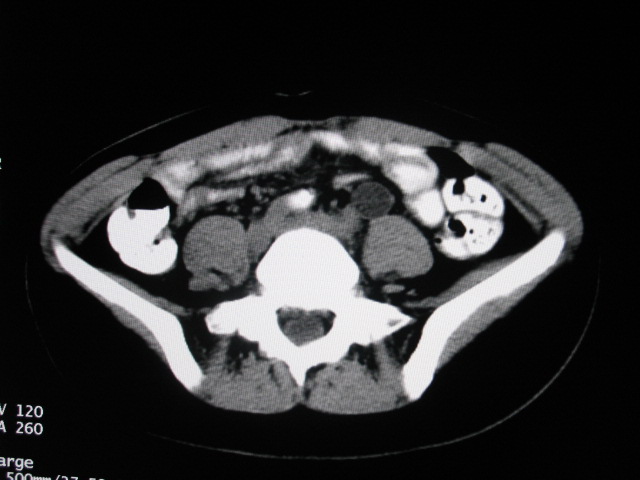

女,28岁,自觉腹部包块一年余

左侧为扩张的输尿管,一直延续到膀胱,那么它的上端应该是扩张的肾盂,但是在他的下方我们看到一个比较正常的肾,所以考虑左侧重复肾盂输尿管畸形。

考虑左侧双肾盂双输尿管畸形,其中一输尿管末端梗阻(不排除异位开口可能)并相应之肾盂及输尿管明显扩张积水。

考虑左侧双肾盂双输尿管畸形,其中一输尿管末端梗阻并输尿管肠管样扩张盂曲、肾盂囊状扩张积水。

支持;左侧双肾盂双输尿管畸形,其中一输尿管末端梗阻并输尿管肠管样扩张迂曲、肾盂囊状扩张积水。

考虑左侧双肾盂双输尿管畸形,其中一输尿管末端梗阻(不排除异位开口可能,不知病人有无不自觉溢尿,有可能开口于阴道或宫颈,也可下端为盲端)并相应之肾盂及输尿管明显扩张积水。

术后证实是左侧双肾盂双输尿管畸形,巨输尿管巨肾盂症